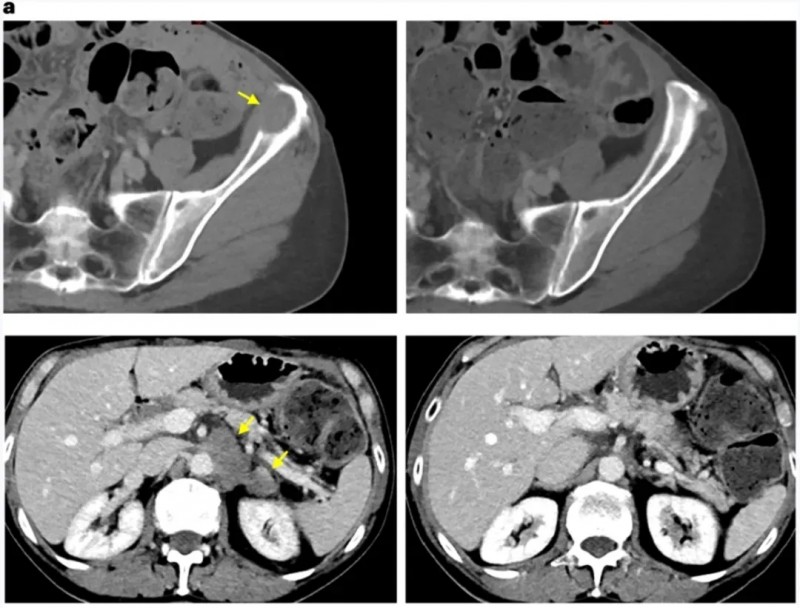

其中一位胆管癌患者,在治疗9个月时,骨骼及主动脉旁淋巴结两处肿瘤均消退,骨转移部位出现愈合迹象,肝脏、肺、肾上腺等其他病灶未在检查中呈现。

▲图源“Nat Med”,版权归原作者所有,如无意中侵犯了知识产权,请联系我们删除

另一位直肠癌患者,在治疗10个月时,肝脏两处肿瘤均缩小,肺部和淋巴结虽存在其他病灶,但未在检查中体现。

最后一位结肠癌患者,在治疗7个月时,右肺、左肺两处结节完全消退,其余结节也有所缩小。